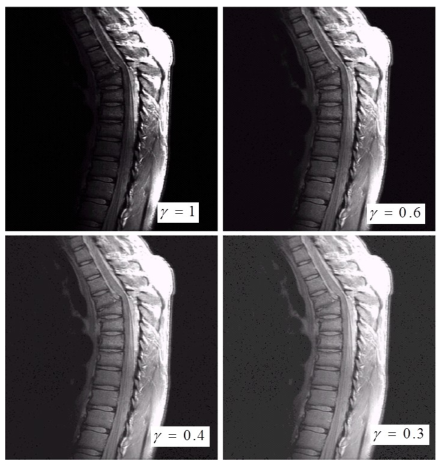

2)应用例子1:伽马校正

3)应用例子2 :对比度增强

(1)γ<1(暗变亮)

(2)γ>1(亮变暗)